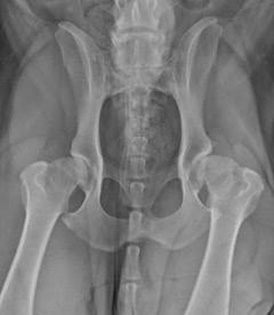

It’s all in the hips - canine hip dysplasia

When compared to humans, dogs grow at an alarmingly quick rate, reaching almost full size before they are a year old. As giant and large breed dogs have such a short time to develop, they grow so rapidly that it can affect their joints and bones. This often results in life long disorders and causes them a lot of pain and discomfort. So let’s get the ball rolling with one condition we’re sure you’ve probably heard of: hip dysplasia!Hip dysplasia is the most common developmental problem affecting the skeleton of dogs. As pups grow, the laxity of their hips (how well the head of the femur and the socket in the pelvis fit together) is the single most important risk factor for the development of arthritis. Loose hips develop arthritis quickly - the cartilage lining inside the joint gets eroded away, the capsule around the joint gets stretched and the head of the femur can start popping out of the socket.

This leads to the signs of hip dyplasia - some of which are: a rolling hip motion when walking, bunny hopping when running, not climbing the stairs at home, not wanting to play. All of these signs are uncomfortable for the pup and as things progress, will get downright painful.

What is hip dysplasia?

For anyone who can remember basic anatomy from school, the hip joint is made up of a ball and socket. Hip dysplasia occurs when the hip joints have not developed normally causing additional friction between the ball and socket. The deterioration of these joints can lead to osteoarthritis and loss of function in the hips.

Spot hip pain while they’re still young

Hip dysplasia in dogs is most frequently associated with large breeds such as German Shepherds, Labradors, Rottweilers and Labradoodles. However, it can affect small and medium dogs too.

It often begins while the dog is still young and physically immature, usually between the ages of 8 to 12 months old (however there are reports as early as 4 months in severe cases). It is always best to treat hip dysplasia before arthritis sets in; although it can be difficult to notice that your puppy is lame, particularly if both hips are affected.

How is hip dysplasia diagnosed?

Specialist orthopaedic vets can diagnose hip dysplasia in dogs quicker than most, particularly in young dogs showing less obvious symptoms. They will perform a thorough orthopaedic examination, and usually carry out x-rays or a CT scan.

How is hip dysplasia in dogs treated?

Hip dysplasia can be treated either surgically or medically.

For young dogs, there is a minimally invasive procedure called Juvenile Pubic Symphysiodesis (JPS). JPS involves fusing a small part of bone in the mid section of the pelvis, so that as the pup continues growing, the hip sockets rotate, keeping the head of the femur snug in the joint, stopping the erosion of the cartilage.

Pups with mild to moderate hip laxity are the ones that tend to benefit the most, and these pups are best identified by veterinary examination and PennHIP xrays to calculate their Distraction Index (which measures how loose their hips are).

Because the operation relies on the hip sockets rotating into place as the pup continues growing, the procedure needs to be performed at an early stage - for medium/large breeds by their 16th week (4 months old) and for giant breeds by the 20th week (5 months old) - to get the most benefit.

If left too late and arthritis has set in, other surgical procedures include a total hip replacement, which replaces the existing joint with an artificial one, or femoral head and neck excision which removes the head and neck of the femur bone.

If surgery is not an option, pain relief and anti-inflammatory drugs can be used to manage the pain from the arthritis. Swimming (hydrotherapy), physiotherapy and laser treatments are also great ways to alleviate discomfort.

Is your puppy at risk?

If your puppy is at high risk for developing hip dysplasia or you think they could be showing signs of joint pain, then have a chat with your usual vet about possibly seeing an orthopaedic specialist.